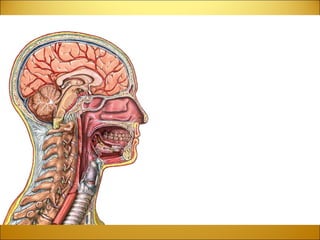

DIENCEPHALON Function :   Chewing  Directs Sense Impulses Throughout the Body  Equilibrium  Eye Movement, Vision  Facial Sensation  Hearing  Phonation  Respiration  Salivation, Swallowing  Smell, Taste   Location :   The diencephalon is located between the cerebral hemispheres and above the midbrain Structures :   Structures of the diencephalon include  the thalamus, hypothalamus, the optic tracts, optic chiasma, infundibulum, 3 rd  Ventricle, mammillary bodies, posterior pituitary gland and the pineal gland.

DIENCEPHALON The  thalamus  is a major relay center to the cortex for all sensations (sight, etc) except for smell.  The  hypothalamus  controls many functions including hunger, thirst, pain, pleasure and the sex drive.  Another key function of the hypothalamus is to regulate the pituitary gland, which in turn, regulates hormonal levels in the body.